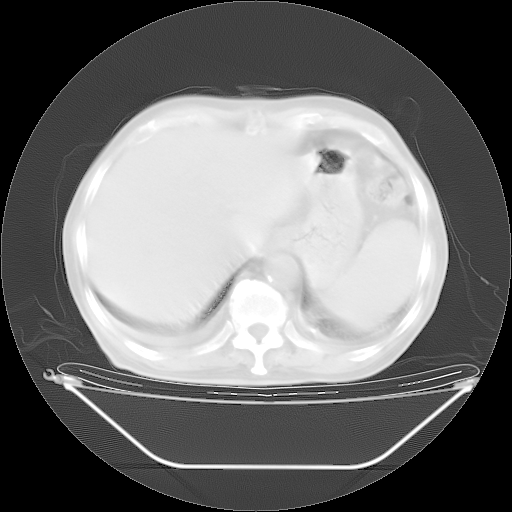

5月9日肺部CT(在4月27日齐鲁医院肺部CT描述部分肺组织磨玻璃样改变,12天后肺组织广泛磨玻璃样改变)

2009年5月9日肺部CT

大致读了系列胸部CT:纵隔窗无明显异常,肺窗:从4、27至今:主要是双肺中下野外带可见毛玻璃样改变,目前处于急性肺泡炎阶段,至于原因考虑1、结替组织或胶原血管性疾病所致?2、恶性疾病如恶组在肺部所致的表现或细支气管肺泡癌?3、药物或其它原因如肺蛋白沉着症所致肺泡炎目前不太可能?总之,明天就去请我院的呼吸科、感染科、血液科和临免专家会诊哈。